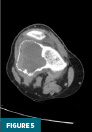

CT of the right knee without IV contrast showed a heterogenous mass within the lateral aspect of the distal femur centered in the metaphysis and extending into the epiphysis. This mass measured 7.1 cm x 6.7 cm x 6.1 cm. There was associated cortical thinning, heterogenous cortical disruption (most prominent along the supralateral aspect), and endosteal scalloping along the margins (Figures 3–5).

Radiographs, CT, and MRI all contribute to establishing the diagnosis. Radiographically, GCTB lesions are typically lytic and eccentric, arising in the metaphysis of long bones and extending into the epiphysis, often to the subarticular bone. Most lesions are geographic with a narrow transition zone. A sclerotic margin is usually absent, although up to 5% of cases demonstrate sclerosis. CT is useful for evaluating cortical thinning and breakthrough, as illustrated in this case. On MRI, lesions typically demonstrate low to intermediate signal intensity on T1-weighted images and demonstrate inhomogeneous signal intensity on T2/STIR sequences, due to hemorrhage or collagen content. Postcontrast images reveal heterogeneous enhancement. These features were evident in our patient’s imaging and were central to guiding the diagnosis.